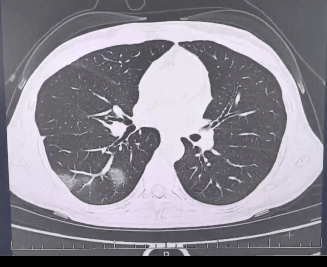

检查结果显示十大虚拟币中文名,

程女士的好几叶肺

都出现了“白肺”现象十大虚拟币中文名,

指间血氧饱和度只有 88%十大虚拟币中文名,

血心肌酶谱、肌钙蛋白的指标、肝功能的指标

也出现了明显的异常十大虚拟币中文名。

确诊流感(重型)十大虚拟币中文名!

图源:杭州市第三人民医院微信公众号